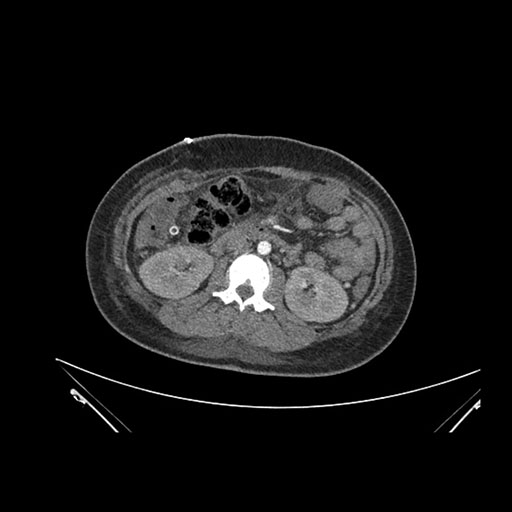

Coronal Venous